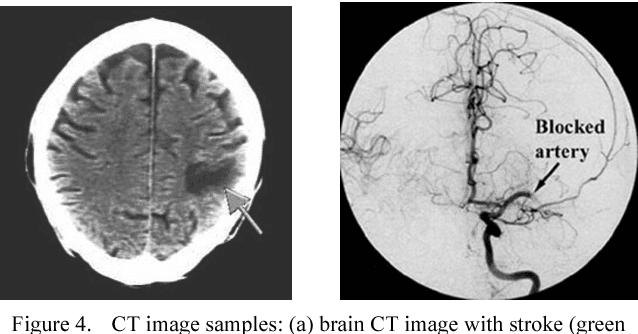

We present a new system based on tracking the temporal evolution of stroke lesions using an image registration technique on CT exams of the patient's brain. The system is able to compare past CT exams with the most recent one related to stroke event in order to evaluate past lesions which are not related to stroke. Then, it can compare recent CT exams related to the current stroke for assessing the evolution of the lesion over time. A new similarity measure is also introduced for the comparison of the source and target images during image registration. It will result in a cheaper, faster and more accessible evaluation of the acute phase of the stroke overcoming the current limitations of the proposed systems in the state-of-the-art.